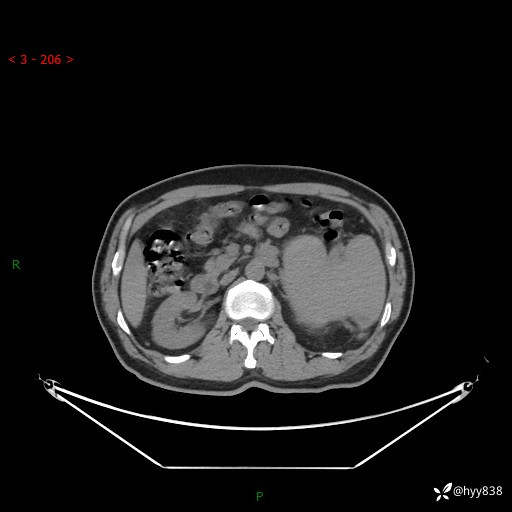

上腹部CT平扫

增强(动脉期+静脉期)